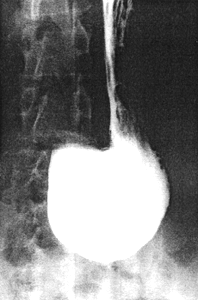

Case 20.1.J.B., 47 year old male. After swallowing the first 3 mouthfuls of Micropaque in the erect position, the stomach was seen to be of the long, hanging, atonic type, the sagging greater curvature forming the most dependent part (Fig. 20.1A). The distal part of the stomach curved upwards and was filled up to the presumed position of the pyloric ring. Peristalsis and cyclical contractions of the pyloric sphincteric cylinder were absent, with total absence of gastric emptying for the first 5 minutes. This would have been interpreted as "pylorospasm" by many investigators. The head of the examining table was then lowered to an angle of 45 degrees, while the patient was rotated 45 degrees onto the right side (i.e. the tilted left anterior oblique radiological position). Immediate emptying of liquid barium occurred in the continued absence of both peristalsis and contractions of the pyloric sphincteric cylinder, revealing a normal pyloric ring surrounding a patent aperture (Fig 21.1B). On re-assuming the erect position, gastric emptying ceased once again.

| Fig. 20.1. A Case J.B. Erect position. Long, atonic stomach, the sagging greater curvature forming most dependent part. Absence of peristalsis, cyclical activity of sphincteric cylinder and emptying of fluid barium. B Case J.B. Oblique tilted position. Normal pyloric ring and patent aperture. Immediate emptying of fluid barium in continued absence of peristalsis and cyclical activity of sphincteric cylinder | |

In 49 of the patients the features were identical to the case quoted. The findings show that the delay in gastric emptying was not due to pylorospasm, in the sense that the pyloric ring was spastic, as neither spasm nor delayed emptying was present in the tilted oblique position; it would be highly improbable for spasm to manifest itself in the erect position only. It was much more likely that the delay in gastric emptying was due to one or both of the following factors: (1) primarily aperistaltic, hypotonic stomach; (2) the erect position of the subject. In these cases, in the erect position, the pyloric aperture is at a higher level than the lowermost part of the greater curvature, which bulges downward. While the aperture is patent, the lack of tone (Chap. 19) and/or cyclical contractions of the pyloric sphincteric cylinder (Chap. 18) causes failure of emptying. In the tilted oblique position the aperture is manipulated so as to become the lowermost part of the stomach. While contractions of the cylinder remain absent, passive, gravitational emptying of liquid content occurs, showing the aperture to be patent, without evidence of spasm of the ring. (In one of the 50 cases a delay in gastric emptying occurred in both the erect and the tilted oblique positions; the cause of this remained unclear.)